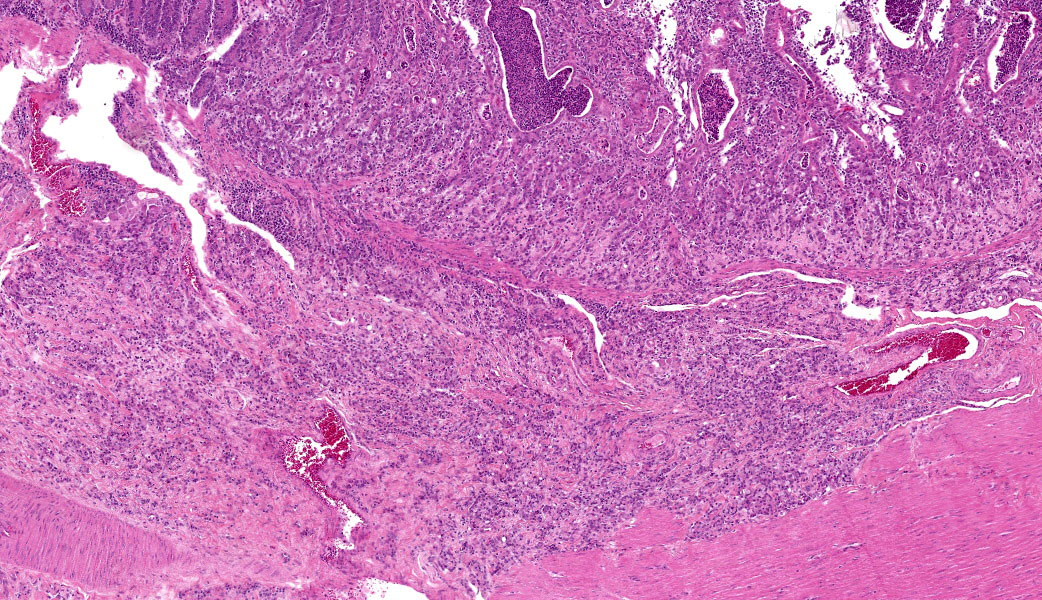

Colon: The lamina propria, submucosa, muscularis mucosa and serosa are markedly expanded by a poorly demarcated, non-encapsulated, infiltrative neoplasm composed of two populations of neoplastic epithelial cells. The neoplastic cells occur singly and in loose packets, lobules and cords, and are supported by variable fibrous stroma containing fibrocytes, fibroblasts and a light basophilic matrix. The predominant neoplastic cell is round to ovoid, 20–50 μm in diameter, with distinct cell borders, abundant finely granular basophilic cytoplasm, peripherally located oval nuclei with lightly stippled pale chromatin and single nucleoli. The secondary type of neoplastic cell is round to oval; 15-30 μm in diameter; with distinct cell borders; moderate amounts of cytoplasm containing small eosinophilic granules; single, peripherally located, large nuclei with coarse chromatin and single nucleoli. Both sub-populations of neoplastic cells exhibit moderate anisocytosis and anisokaryosis. Mitoses are rare (< 1 per HPF). There is moderate expansion of the adventitia of large vessels with neoplastic cells. The lamina propria propria is diffusely expanded by moderate numbers of lymphocytes, plasma cells, occasional macrophages and rare eosinophils. Crypts are often ectatic, lined with attenuated epithelium and containing non-degenerate neutrophils, rare macrophages and lymphocytes (crypt abscess).

- Large intestine, colon: Intestinal adenocarcinoma, sheep (Ovis aries), ruminant.

- Large intestine: Colitis, lymphoplasmacytic, chronic, diffuse, mild, with multifocal crypt abscesses.

Ileocecal junction: Intestinal adenocarcinoma.

This last case is a classic! Many thanks to the contributor for a great submission and write-up. Most participants were readily able to reach a diagnosis of intestinal adenocarcinoma in this case due to the high mitotic rate, degree of invasion the neoplasm into abluminal tissue layers, and the striking desmoplastic response. The deep infiltration from the mucosa outwards allows for a strong argument of a primary intestinal adenocarcinoma rather than a metastatic carcinoma. Intestinal adenocarcinomas tend to invade from the mucosa deep into and run laterally through the submucosa and subsequent layers.

Despite being able to reach a diagnosis, most participants struggled with the specific anatomic location for this tissue. After much back and forth, the consensus amongst conference-goers was that this is likely representative of the ileocecal junction or close to it, since there are features of both small and large intestine on opposite ends of the H&E slide. While there are crypts, mucus glands, and subcutaneous fat consistent with large intestine visible on one side, there are also villi on the other, most clearly seen associated with and around the neoplasm.

Lastly, there are notable mucosal erosions with regional neoplasia-associated architecture disruption that most participants felt was likely the cause of the inflammation present in the slide rather than an additional primary enteritis. As such, this is reflected in the JPC morphologic diagnosis, which focuses solely on the neoplasm and considers the other changes to be secondary.